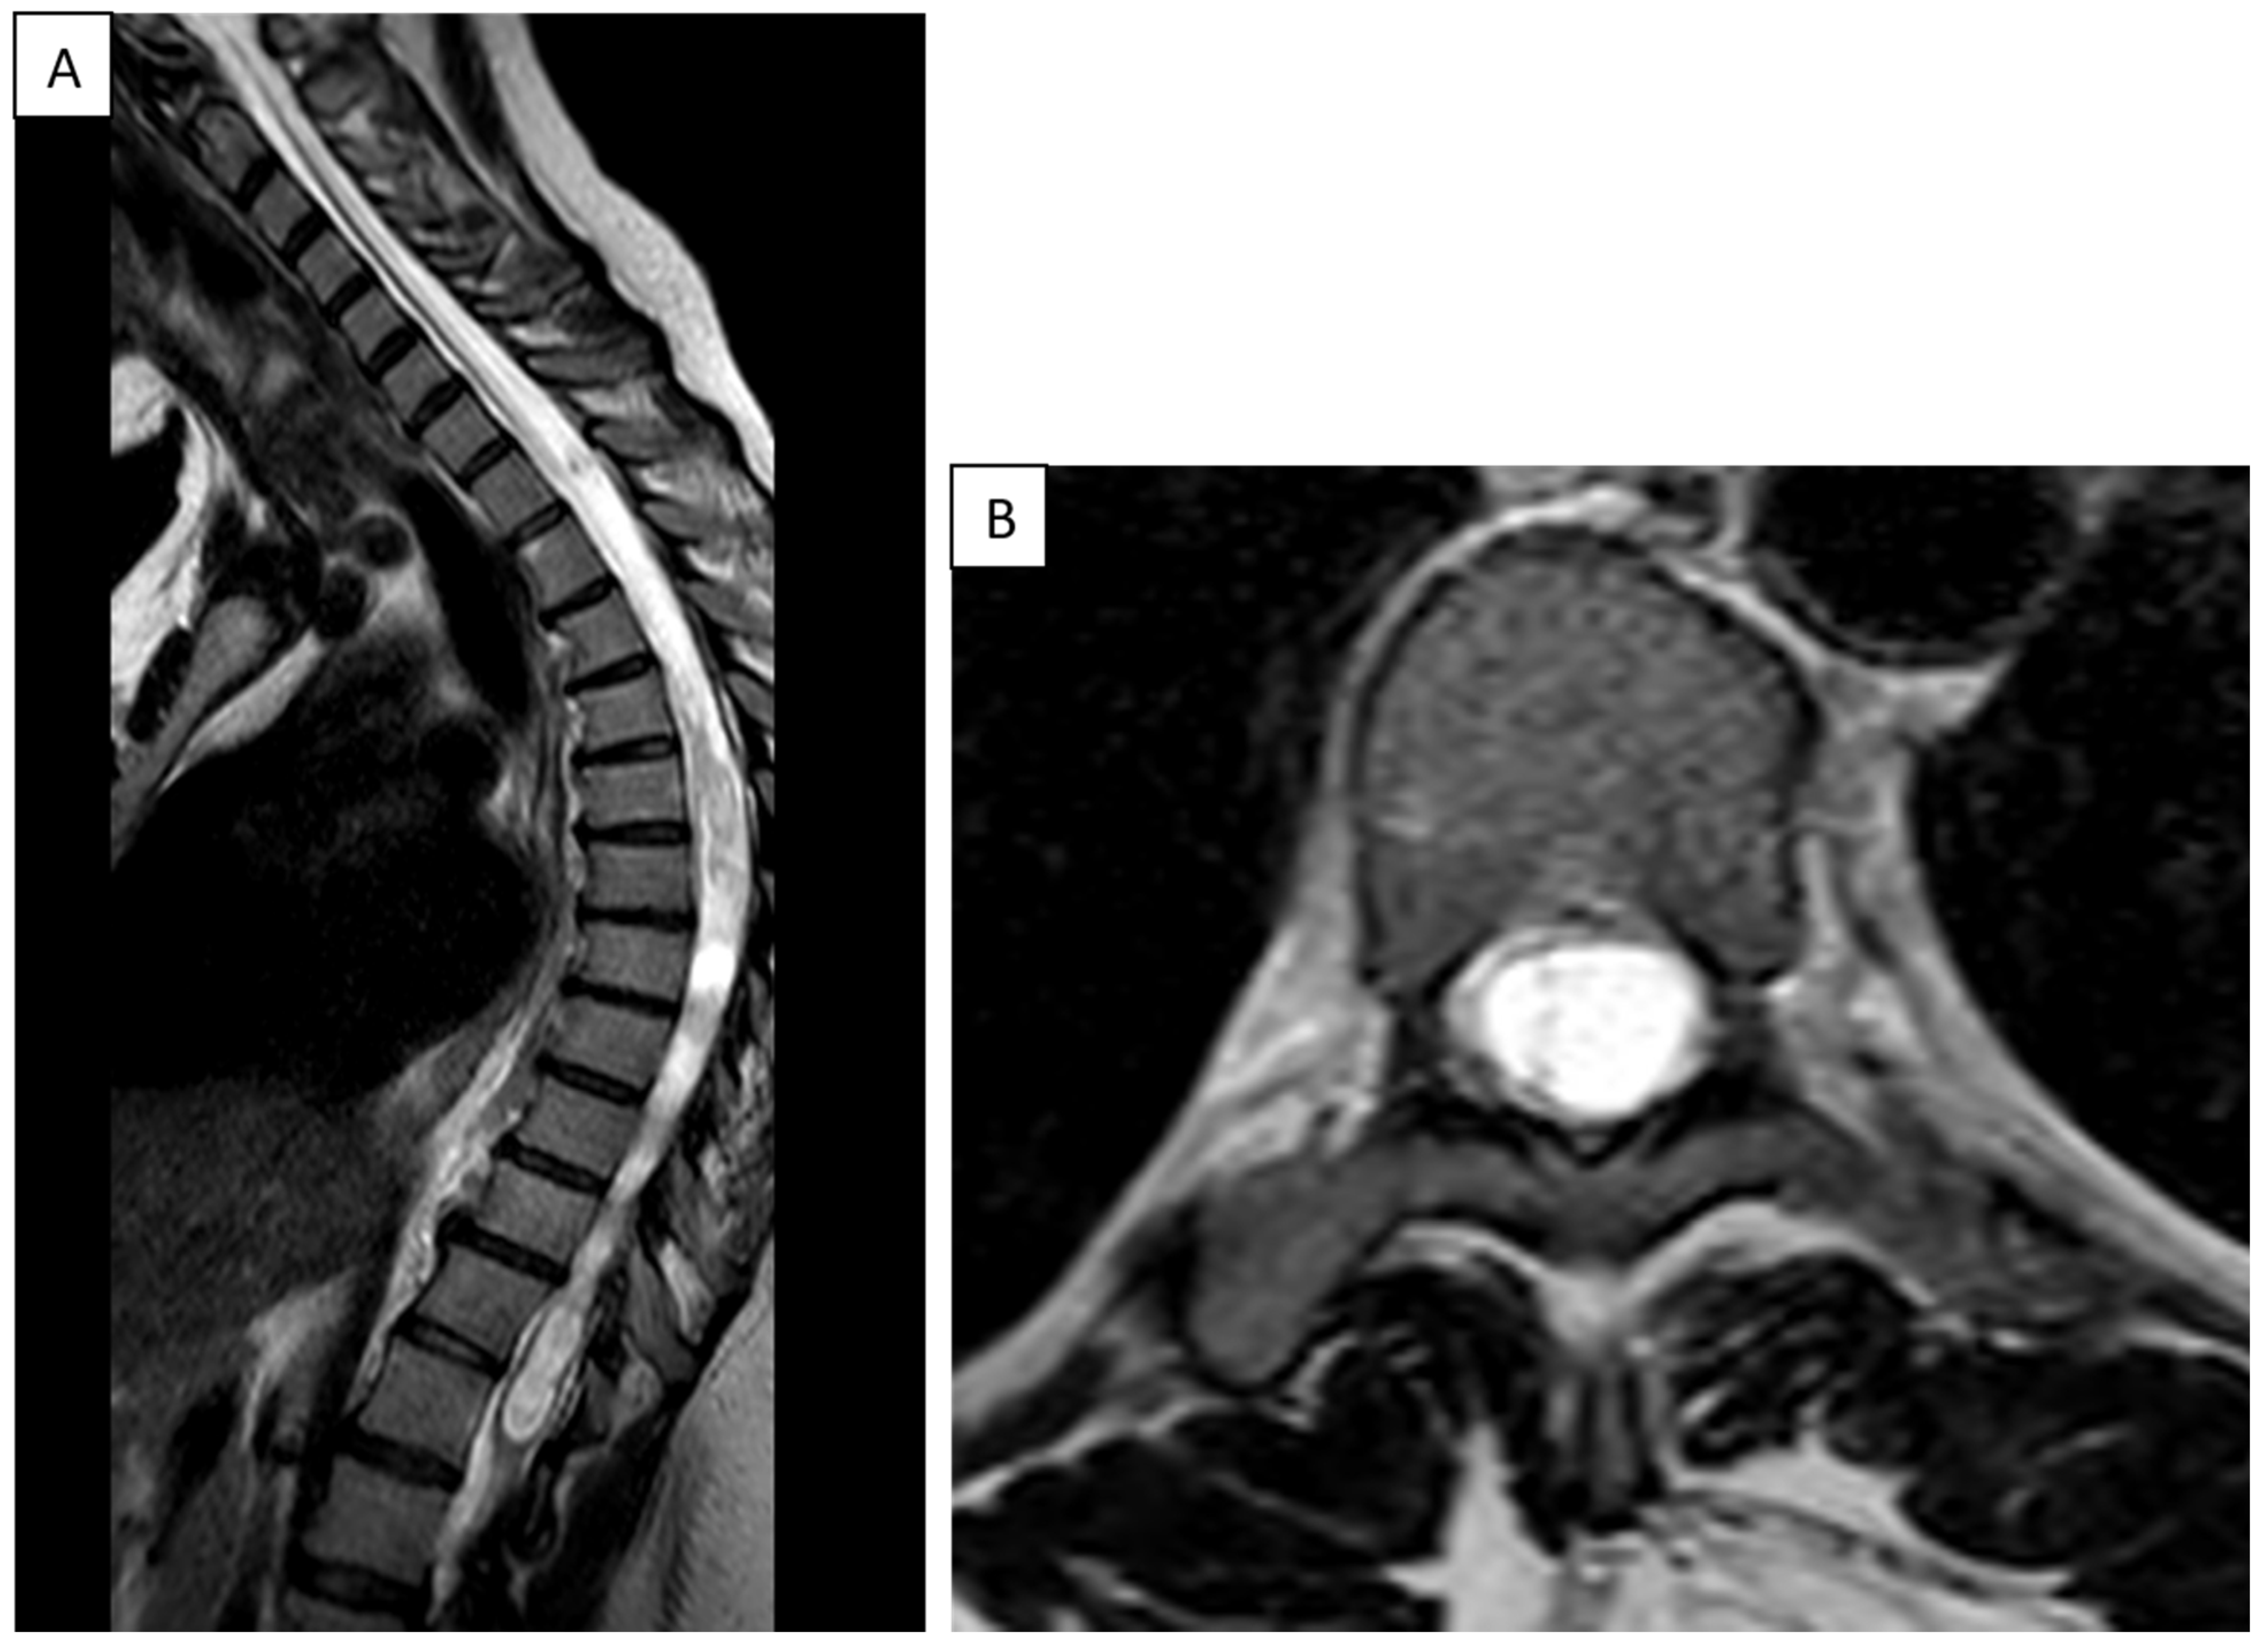

6.4. Illustrative Clinical Case

9. Treatment Considerations in Charcot Shoulder

Back to Our Patient